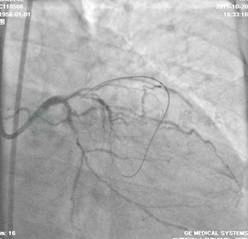

选用右侧桡动脉径路,6F血管鞘。造影发现:右冠优势型供血,三支病变,左主干正常,前降支(LAD)近端处完全闭塞,无明确残端,第一间隔支与闭塞远端第四间隔支形成侧支循环;回旋支中段、OM1中段70%狭窄;右冠近端60%狭窄、中段70%狭窄(图1~图4)。

图1 三支病变,LM正常,LAD近端处完全闭塞,无明确残端